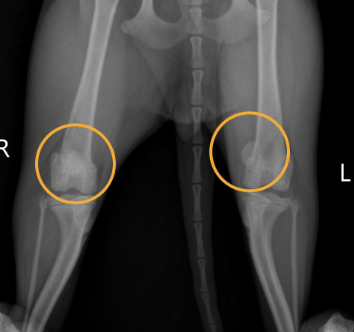

슬개골탈구는 한마디로 무릎뼈가 제자리를 벗어나는 질환입니다.

선천적 요인 혹은 외부 충격, 혹은 반복적인 움직임으로 인해 발생하죠.

초기엔 잘 모르고 지나치기 쉽지만, 방치하면 관절염이나 영구적인 손상까지 올 수 있습니다.